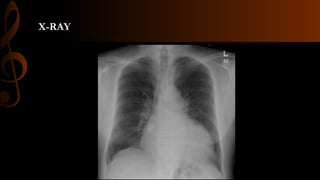

• Рентген зураг

X-RAY